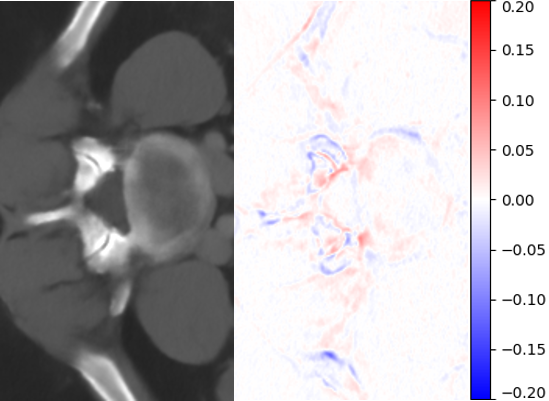

Figure 6: Visual comparisons of different methods against AMI. The difference maps are provided to the right of the results for better visualization. Images are best viewed when magnified.

Table 4 summarizes the performance of different implementations against AMI, evaluated on Isag(x,y,z)subscript𝐼𝑠𝑎𝑔𝑥𝑦𝑧I_{sag}(x,y,z), which we find to have better quantitative results than Icor(x,y,z)subscript𝐼𝑐𝑜𝑟𝑥𝑦𝑧I_{cor}(x,y,z) for all methods. For both rz=4subscript𝑟𝑧4r_{z}=4 and rz=6subscript𝑟𝑧6r_{z}=6, we found improvement in image quality from AMI over other methods, while Meta-SR and RDN have comparable performance. Despite the higher parameter number, MDSR ranked last due to using different substructures for different upsampling factors. For visual demonstration, we can see in Fig. 6 that AMI is able to recover the separation between the bones of the spine, while other methods lead to erroneous recovery where the bones are merged together. Compared to Meta-SR, AMI generates HW𝐻𝑊HW times less filter weights in its filter generation stage. With finite memory, this allows for GPUs to handle more slices in parallel, and achieve faster inference time per volume.